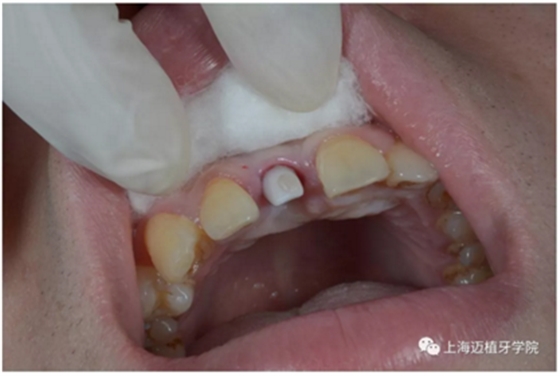

戴牙前口內(nèi)照片:

去除愈合基臺:

口內(nèi)個性化基臺: